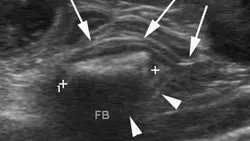

A brief abdominal ultrasound was performed and the foreign body was confirmed in a small intestinal lumen.